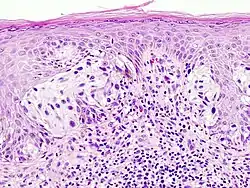

Malignant melanoma of the skin. This is a section of tissue, stained with hematoxylin & eosin, and viewed on a microscope slide.